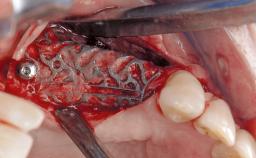

Peri-Implant Mucositis Treatment Outcomes on an Implant with a Submucosal Restoration Margin

Mauricio Araujo and Flauvia Matarazzo present this straightforward clinical case, demonstrating the potential effect of implant placement depth on the resolution of peri-implant treatment. A 42-year-old systemically healthy female patient, a non-smoker with no history of periodontitis, was treated at the Dental Clinic at the State University of Maringá, Brazil between 2008 and 2009, when she received five implants restored with single crowns at sites 14, 26, 27, 36, and 46. After delivery of the implant-supported prosthetic restorations, the patient was enrolled in the supportive peri-implant therapy (SPiT) maintenance program at the same university.